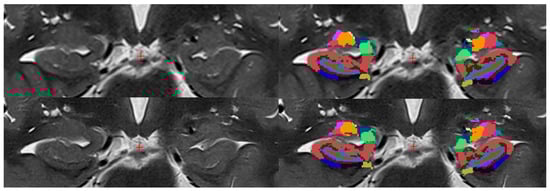

parasubiculum,

HATA,

fimbria,

hippacampal_fissure,

HP_tail,

presubiculum-head,

presubiculum-body,

subiculum-head,

subiculum-body,

CA1-head,

CA1-body,

CA3-head,

CA3-body,

CA4-head,

CA4-body,

GC-ML-DG-head,

GC-ML-DG-body,

molecular_layer_HP-head,

moleculcular_layer_HP-body.